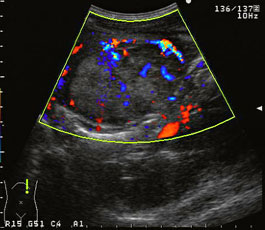

肝細胞癌では腫瘤境界部に沿って血流が観察され腫瘤を包み込むような血管構築が想像できる。 |